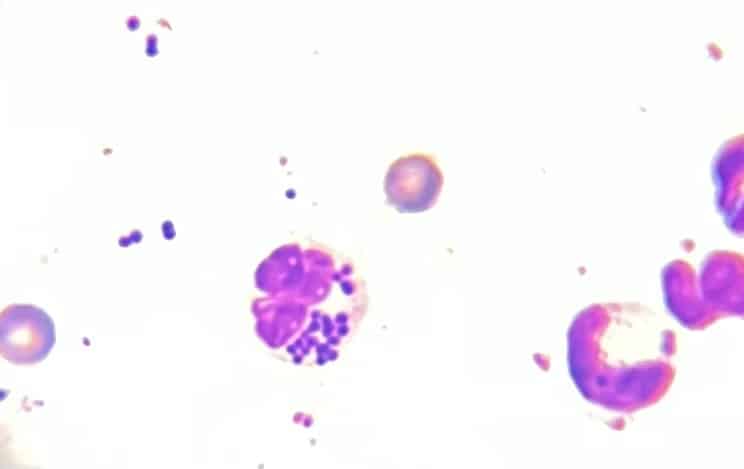

Frottis dermatologie

Image microscopique de bactéries phagocytées dans un globule blanc.